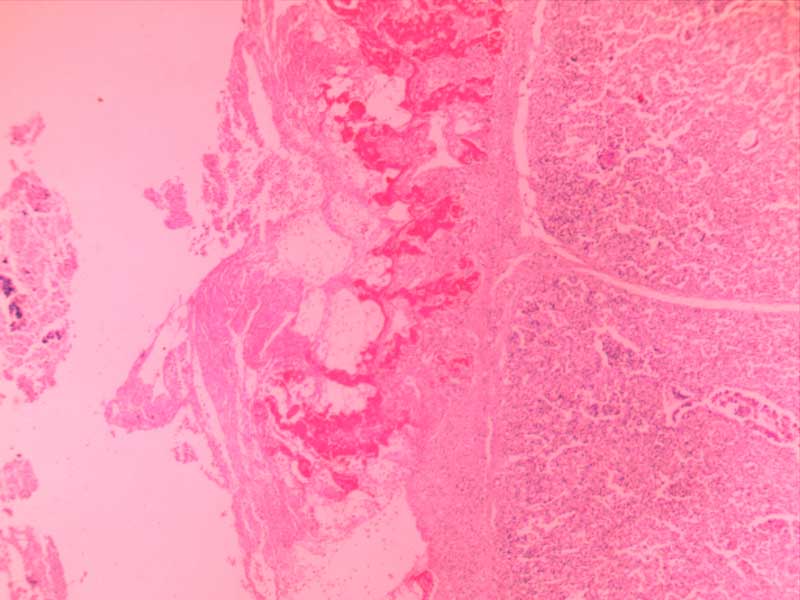

新月体肾炎-(2)